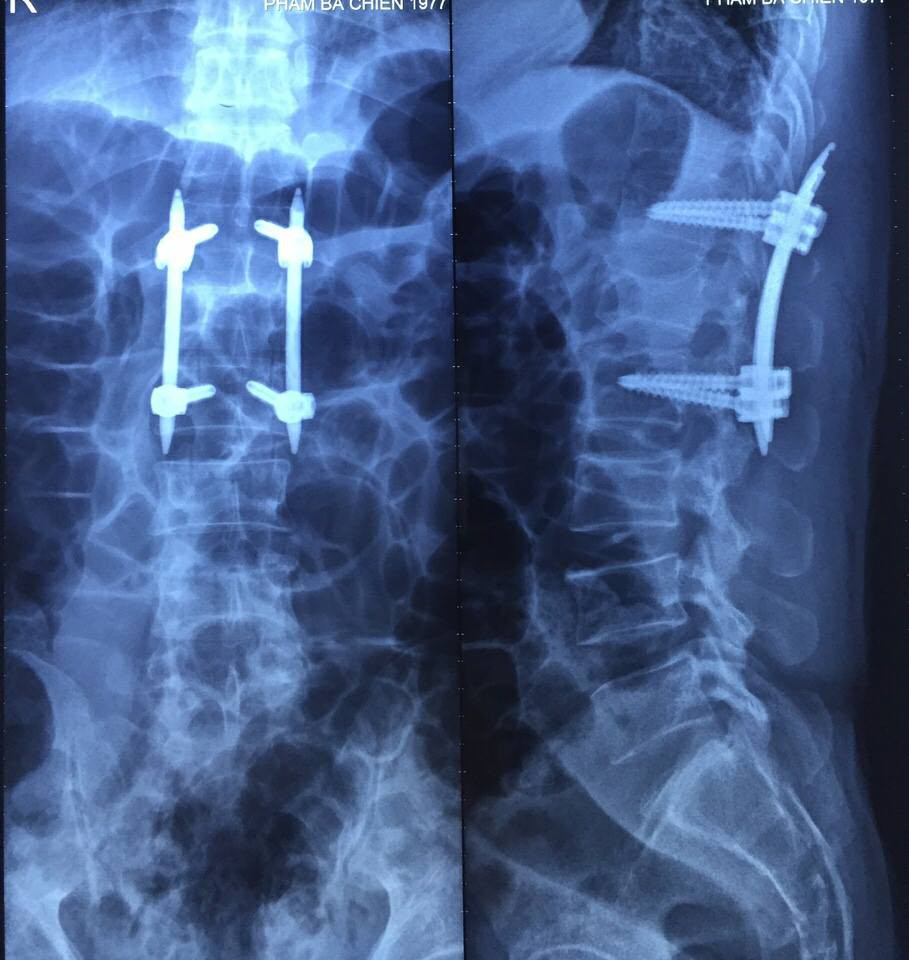

Mới đây, là trường hợp bệnh nhân P.B.C, 40 tuổi, nhập viện cấp cứu ngày 20/11 do tai nạn lao động ngã thang từ độ cao 4m. Qua thăm khám lâm sàng kết hợp với các phương pháp chẩn đoán hình ảnh hiện đại, các bác sĩ chẩn đoán anh C bị chấn thương cột sống - vỡ đốt sống L1 mất vững.

Nhưng nhờ áp dụng phương pháp phẫu thuật cố định cột sống vít qua da bằng hệ thống Sextant vừa được bác sĩ Patrick Suen chuyển giao trước đó, kíp phẫu thuật gồm bác sĩ Phạm Văn Dương và bác sĩ Lương Minh Quang đã rút ngắn thời gian phẫu thuật chỉ còn 1,5h thay vì 2-3h như trước đây.

Ca mổ đã thành công ngoài mong đợi, chỉ sau chưa đầy 48 tiếng, anh P.B.C đã có thể đi lại bình thường, không chút đau đớn hay khó khăn, đường mổ thẩm mỹ với vít qua da chỉ dài tổng cộng khoảng 4cm giúp người bệnh mau chóng hồi phục. Anh C được ra viện chỉ 3 ngày sau phẫu thuật.